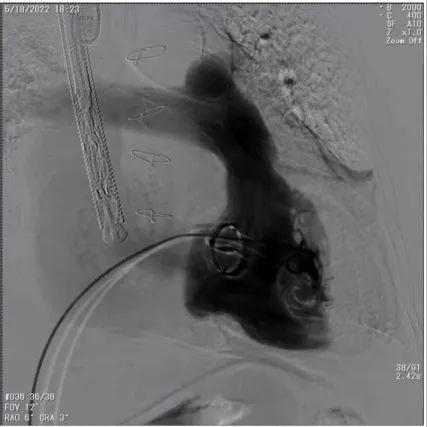

术前DSA造影